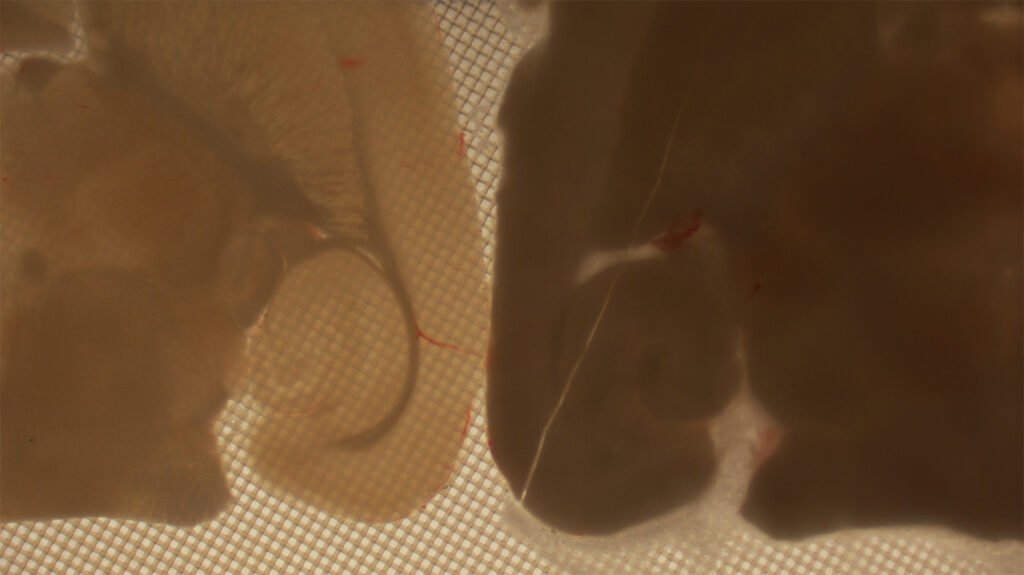

Ces images stéréomicroscopiques montrent des coupes de cerveau à -160 °C. Le tissu de gauche a été préservé par vitrification, tandis que celui de droite a été détruit par cristallisation et fissuration. © Alexander German